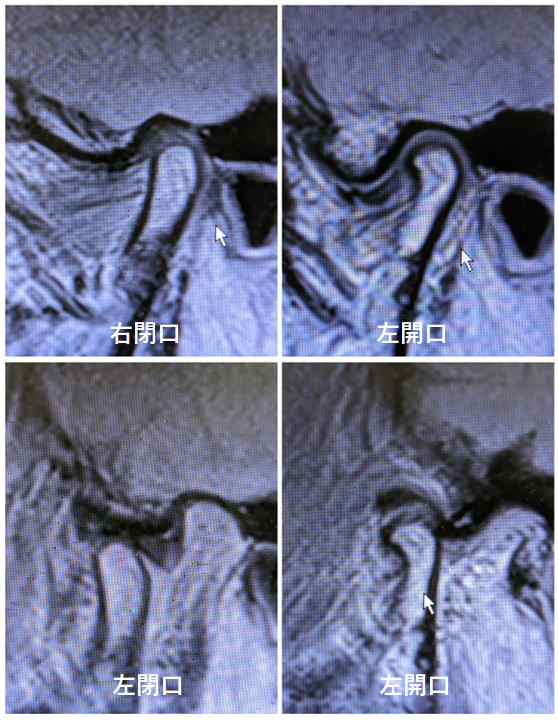

2023年5月 運動療法のポイント 運動量